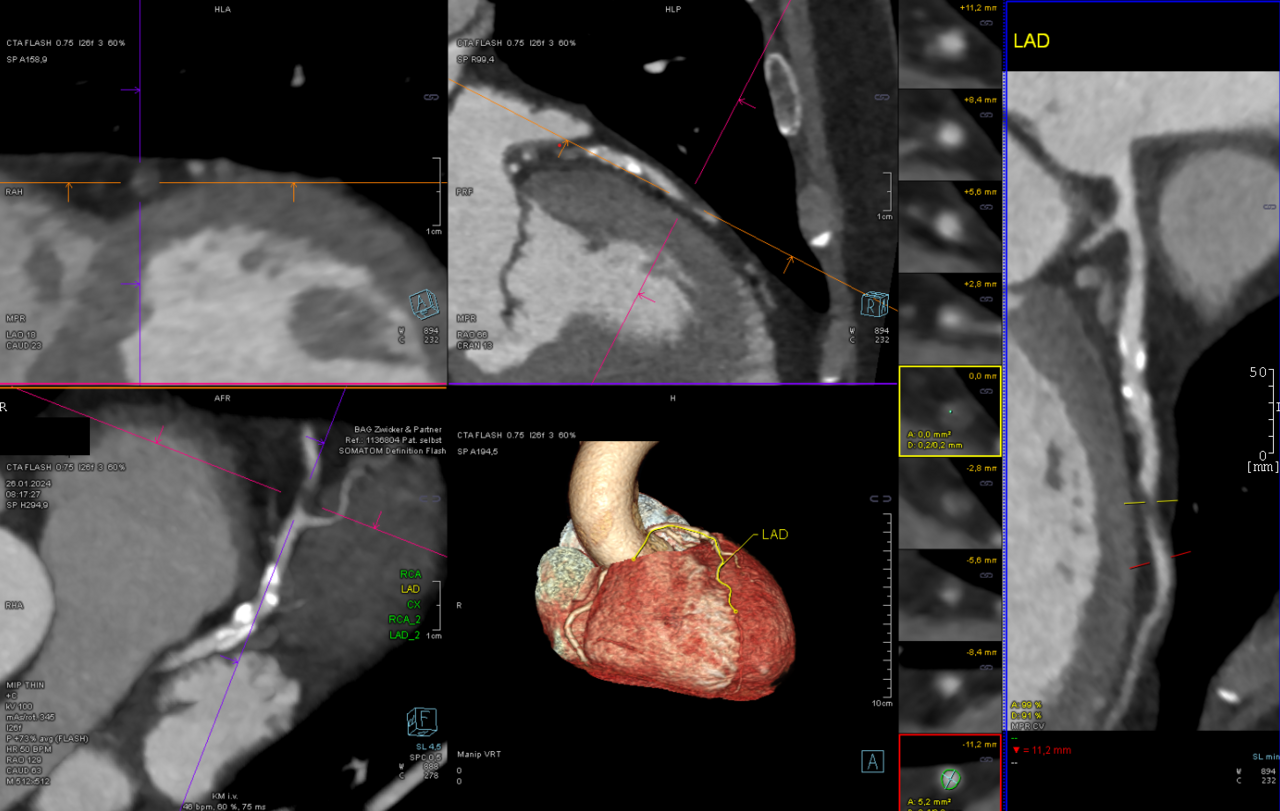

CCTA — CAD-RADS 4a Stenosis

Coronary CT angiography showing severe stenosis (70-99%) graded CAD-RADS 4a

CT Downloaded 2026-03-15

Ct

Cta Coronary 120 kVp

Wikimedia Commons: CCTA CAD-RADS 4a.png